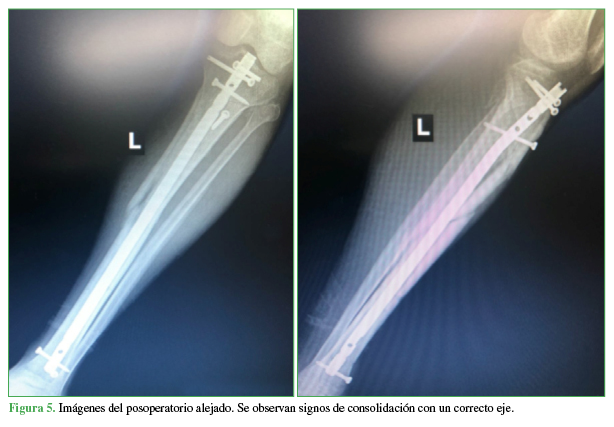

Consolidación

Se logró la consolidación ósea en todos los casos, en un tiempo promedio de 5 meses (mínimo 3, máximo 10). Un paciente (4%) con una fractura segmentaria (caso 4) requirió un aumento del foco proximal con una placa sobre el clavo más el aporte de injerto óseo autólogo para lograr la consolidación ósea (Figura 5).